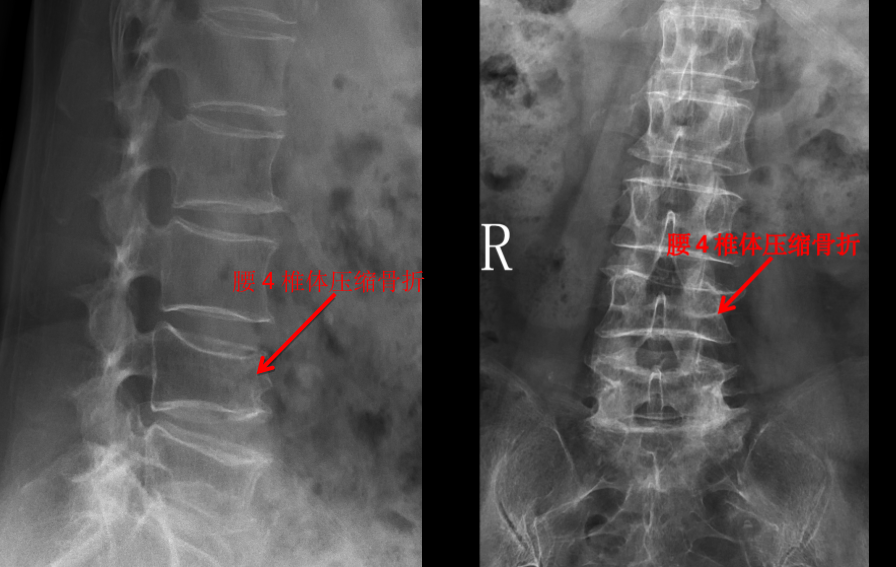

我们管 X 线检查叫 X 光片、照相或拍片。在 X 光片里,我们能看到脊柱有没有骨折,有没有骨质破坏,有没有脊柱侧弯、有没有骨质增生等。一些有经验的大夫,可以通过椎间隙高度的丢失判断椎间盘的退变程度。

但是对于大部分软组织病变如椎间盘、椎管内神经、有没有占位性病变等却无能为力。如果患者有压缩骨折,X 光片也无法判断是新鲜骨折还是陈旧骨折,这样也就无法定制下一步诊疗计划。

前面提到的腰椎压缩骨折,X 光片可以看出楔形变,但无法判断新鲜骨折还是陈旧骨折,进一步完善腰椎 MRI 才能明确诊断,做出下一步治疗计划。